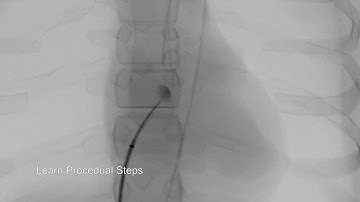

Step by step approach Trans septal puncture with #agilis #EPStudy #AF #ablation